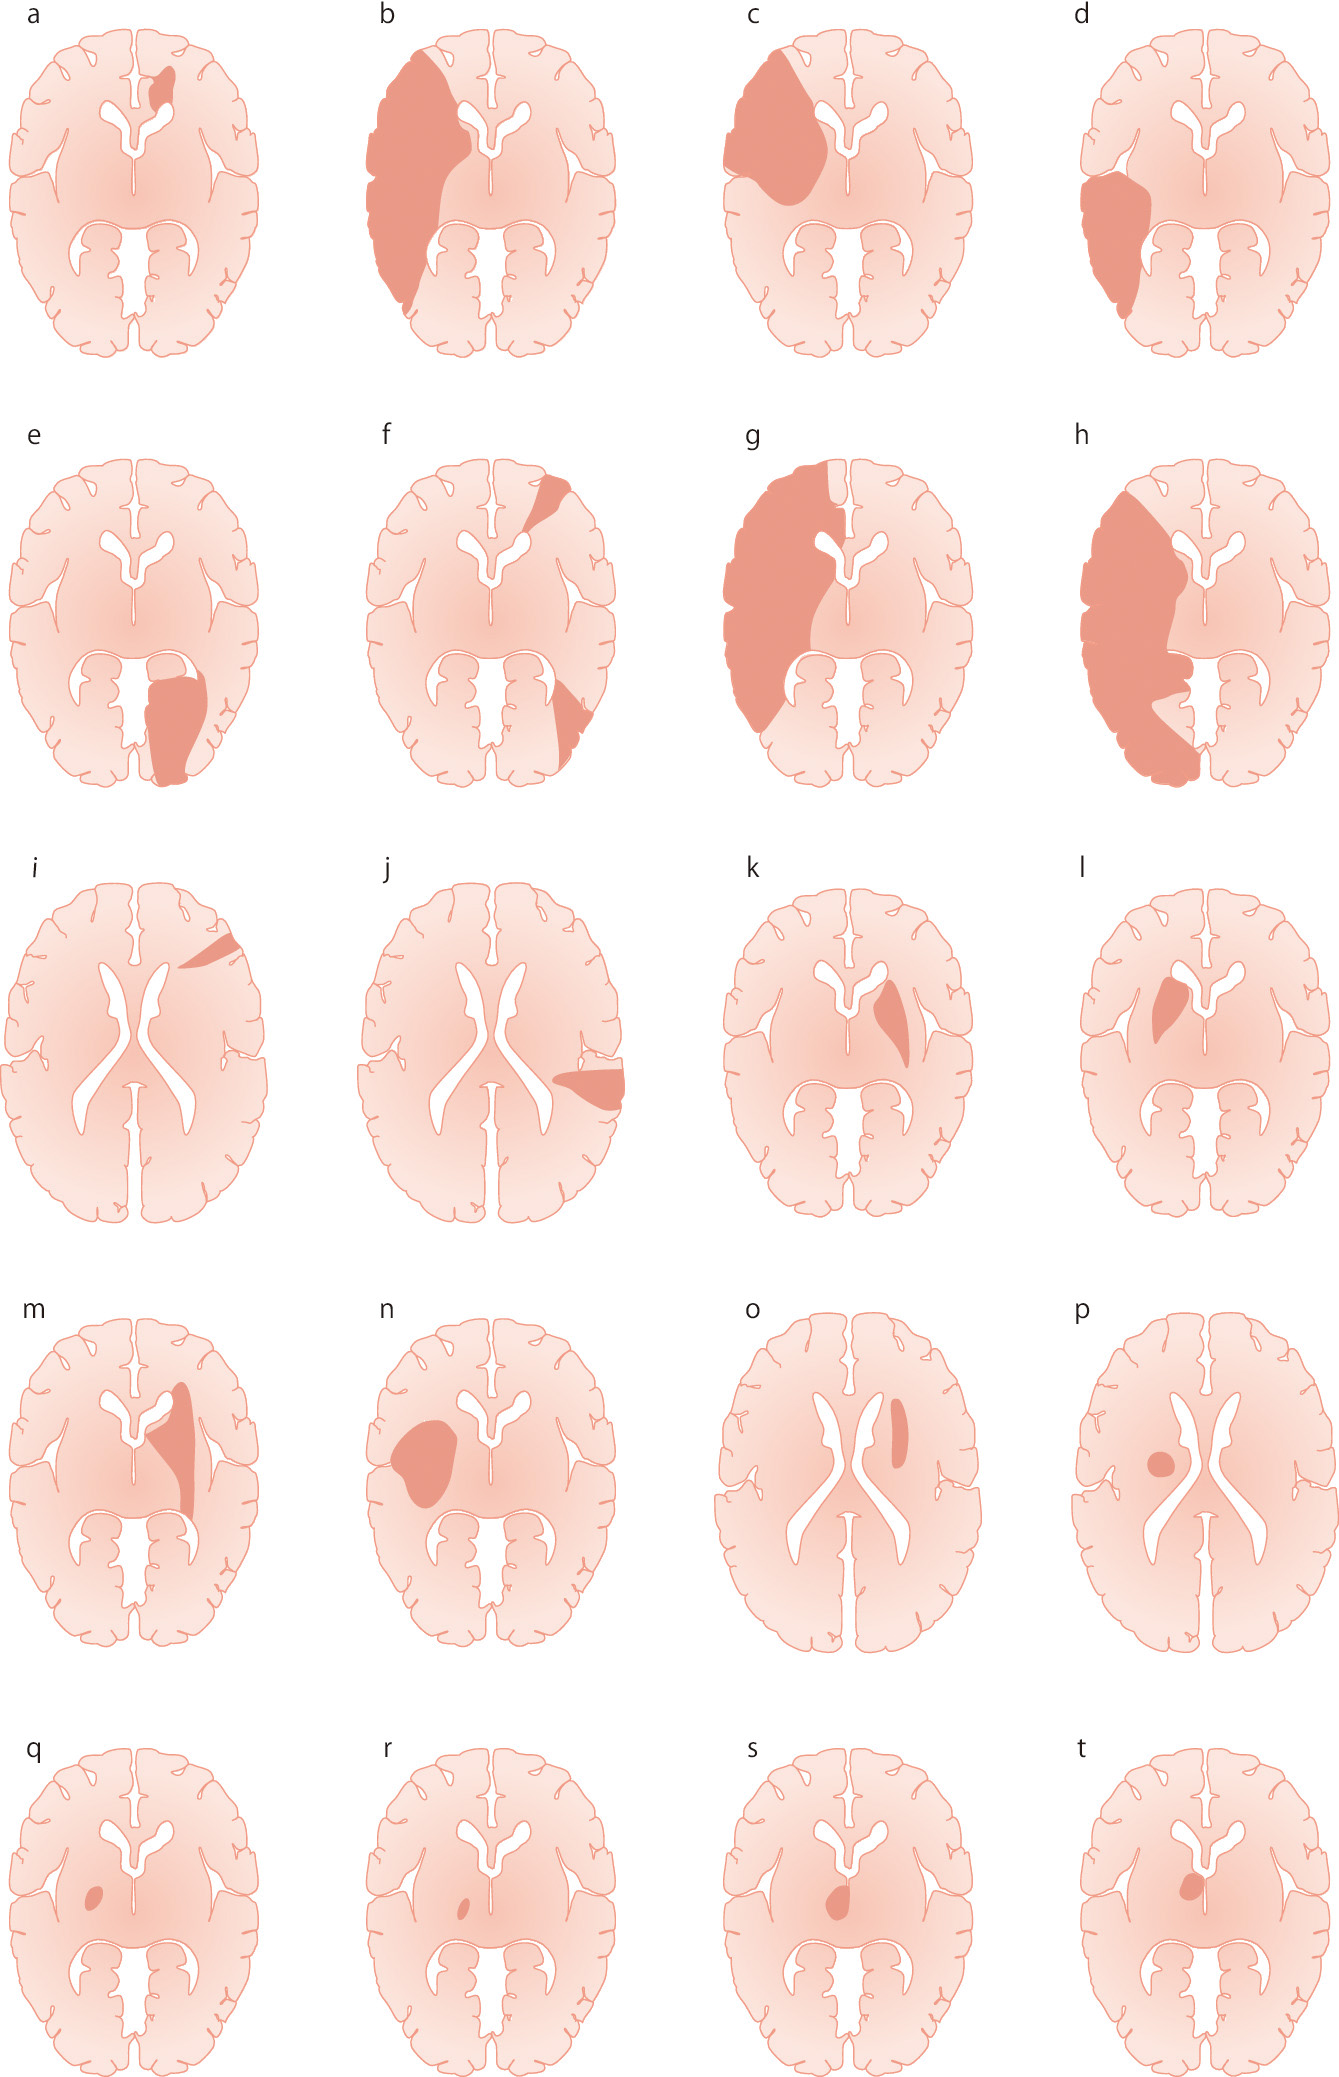

a:前大脳動脈領域梗塞 (血栓性のA2閉塞)

b:中大脳動脈領域全体の梗塞 (塞栓性)

c:中大脳動脈のsuperior trunk領域梗塞 (塞栓性)

d:中大脳動脈のinferior trunk領域梗塞 (塞栓性)

e:後大脳動脈領域梗塞 (塞栓性)

f:分水嶺梗塞 (血栓性内頸動脈閉塞)

g:2枝病変:前大脳動脈領域と中大脳動脈領域 (塞栓性)

h:2枝病変:中大脳動脈領域と後大脳動脈領域 (塞栓性)

i:軟膜動脈領域梗塞 (塞栓性)

j:軟膜動脈領域梗塞 (塞栓性)

k:線条体内包梗塞 (塞栓性あるいは血栓性中大脳動脈閉塞)

l:線条体内包梗塞 (塞栓性あるいは血栓性中大脳動脈閉塞)

m:extended large subcortical infarct (血栓性内頸動脈閉塞)

n:extended large subcortical infarct (血栓性中大脳動脈閉塞)

o:終末領域梗塞 (血栓性内頸動脈閉塞)

p:ラクナ梗塞:pure motor hemiparesis (血栓性)

q:ラクナ梗塞:pure motor hemiparesis (血栓性)

r:視床梗塞:inferolateral infarct (血栓性)

s:視床梗塞:paramedian thalamic infarct (塞栓性)

t:視床梗塞:tuberothalamic infarct (血栓性)